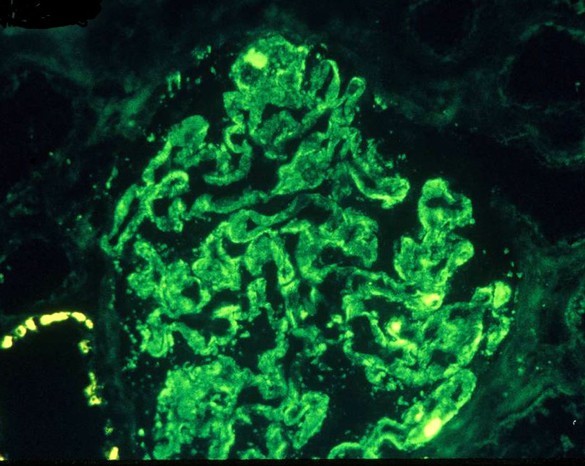

PT is a 56-year old woman with no significant medical history who presents with 2 months of LE swelling, nocturia and foamy urine

On exam, BP 138/76, periorbital edema, 3+ pitting edema of LE

Laboratory studies: Cr 1.3, TC 556, Albumin 1.8, Ur Protein: Cr ratio 13, C3 135, C4 38

HIV, HBV, HCV, ANA all negative

IgM deposition noted in histologic sample below. What is her diagnosis and treatment?

Immunofluorescence:

- Trapping of IgM within mesangium